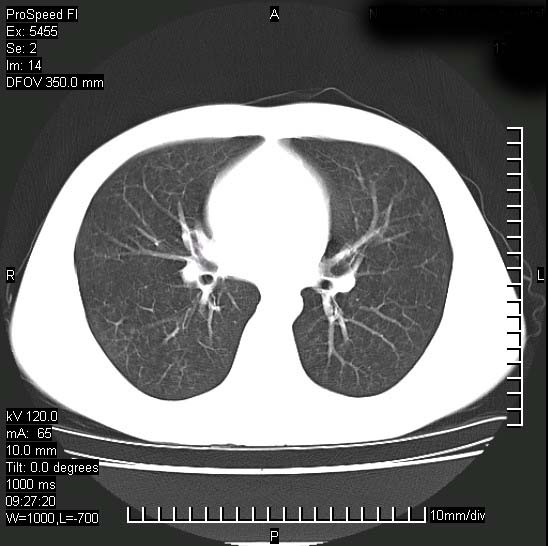

以下是引用zjzjr在2008-12-3 20:50:00的发言:[br]考虑泛细支气管肺炎,建议进一步检查除外肺出血性疾病如含铁血黄素沉着症、肺肾综合征等。

以下是引用zjzjr在2008-12-3 20:50:00的发言:[br]考虑泛细支气管肺炎,建议进一步检查除外肺出血性疾病如含铁血黄素沉着症、肺肾综合征等。

以下是引用光线在2008-12-3 20:19:00的发言:[br]双肺间质性改变。